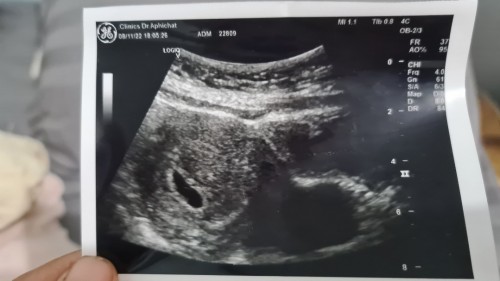

ท้องลมมาก่อน ตอนนี้ท้อง 5W+ ไปซาว หมอบอกยังมองไม่เห็น ให้มาซาวใหม่ กังวลคะ กลัวจะท้องลมต่อมีโอกาส ?

เคยมีใครท้องลม ติดต่อกัน 2 ท้องมั้ยคะ ? ตอนนี้อาการแค่หายใจเหนื่อย เหม็นกลิ่นตุตุ ขมปาก ลิ้นแห้ง ไม่คัดเต้า ไม่ฉี่บ่อย ไม่คลื่นไส้ ไม่อ้วก หมอนัดอีกที 22/11 กังวลมากคะ